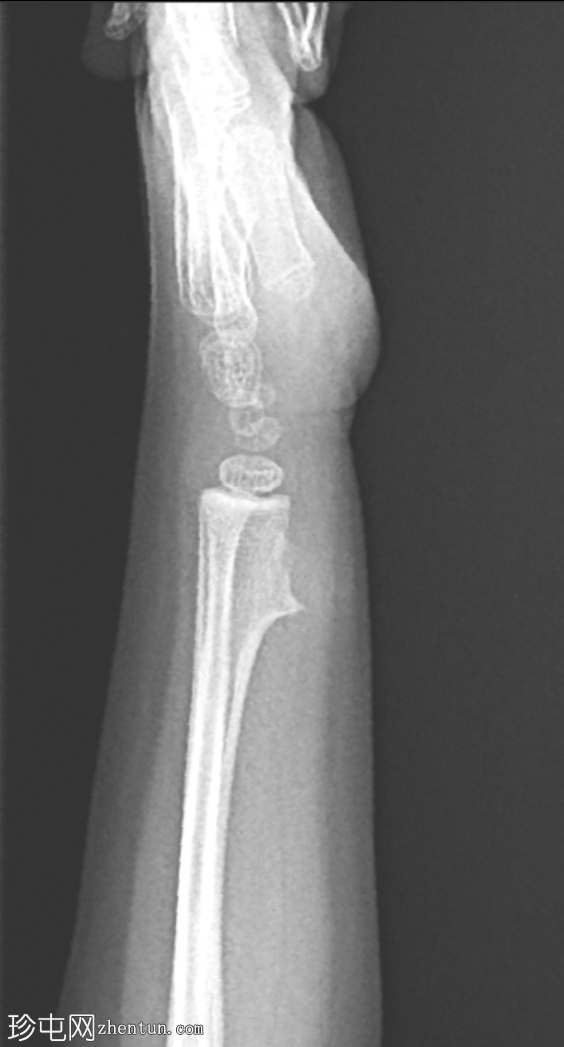

侧位片

可见桡骨远端干骺端前外侧有一骨性增生。病变与母骨皮质和髓质相连。边界清晰。无皮质破损、骨膜反应及相关软组织肿块。邻近尺骨外观正常。无骨折或脱位。